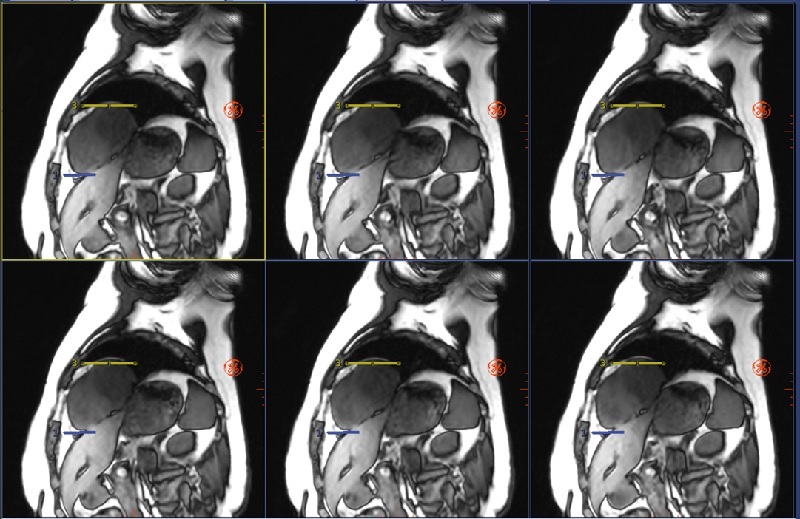

| Top/Bottom | Description |

|---|---|

| Top images Motion Compensation On |

Note how the heart is in the same position relative to the yellow/blue lines from one image to the next. |

| Bottom images Motion Compensation Off |

Note how the heart moves relative to the yellow/blue lines from one image to the next. |